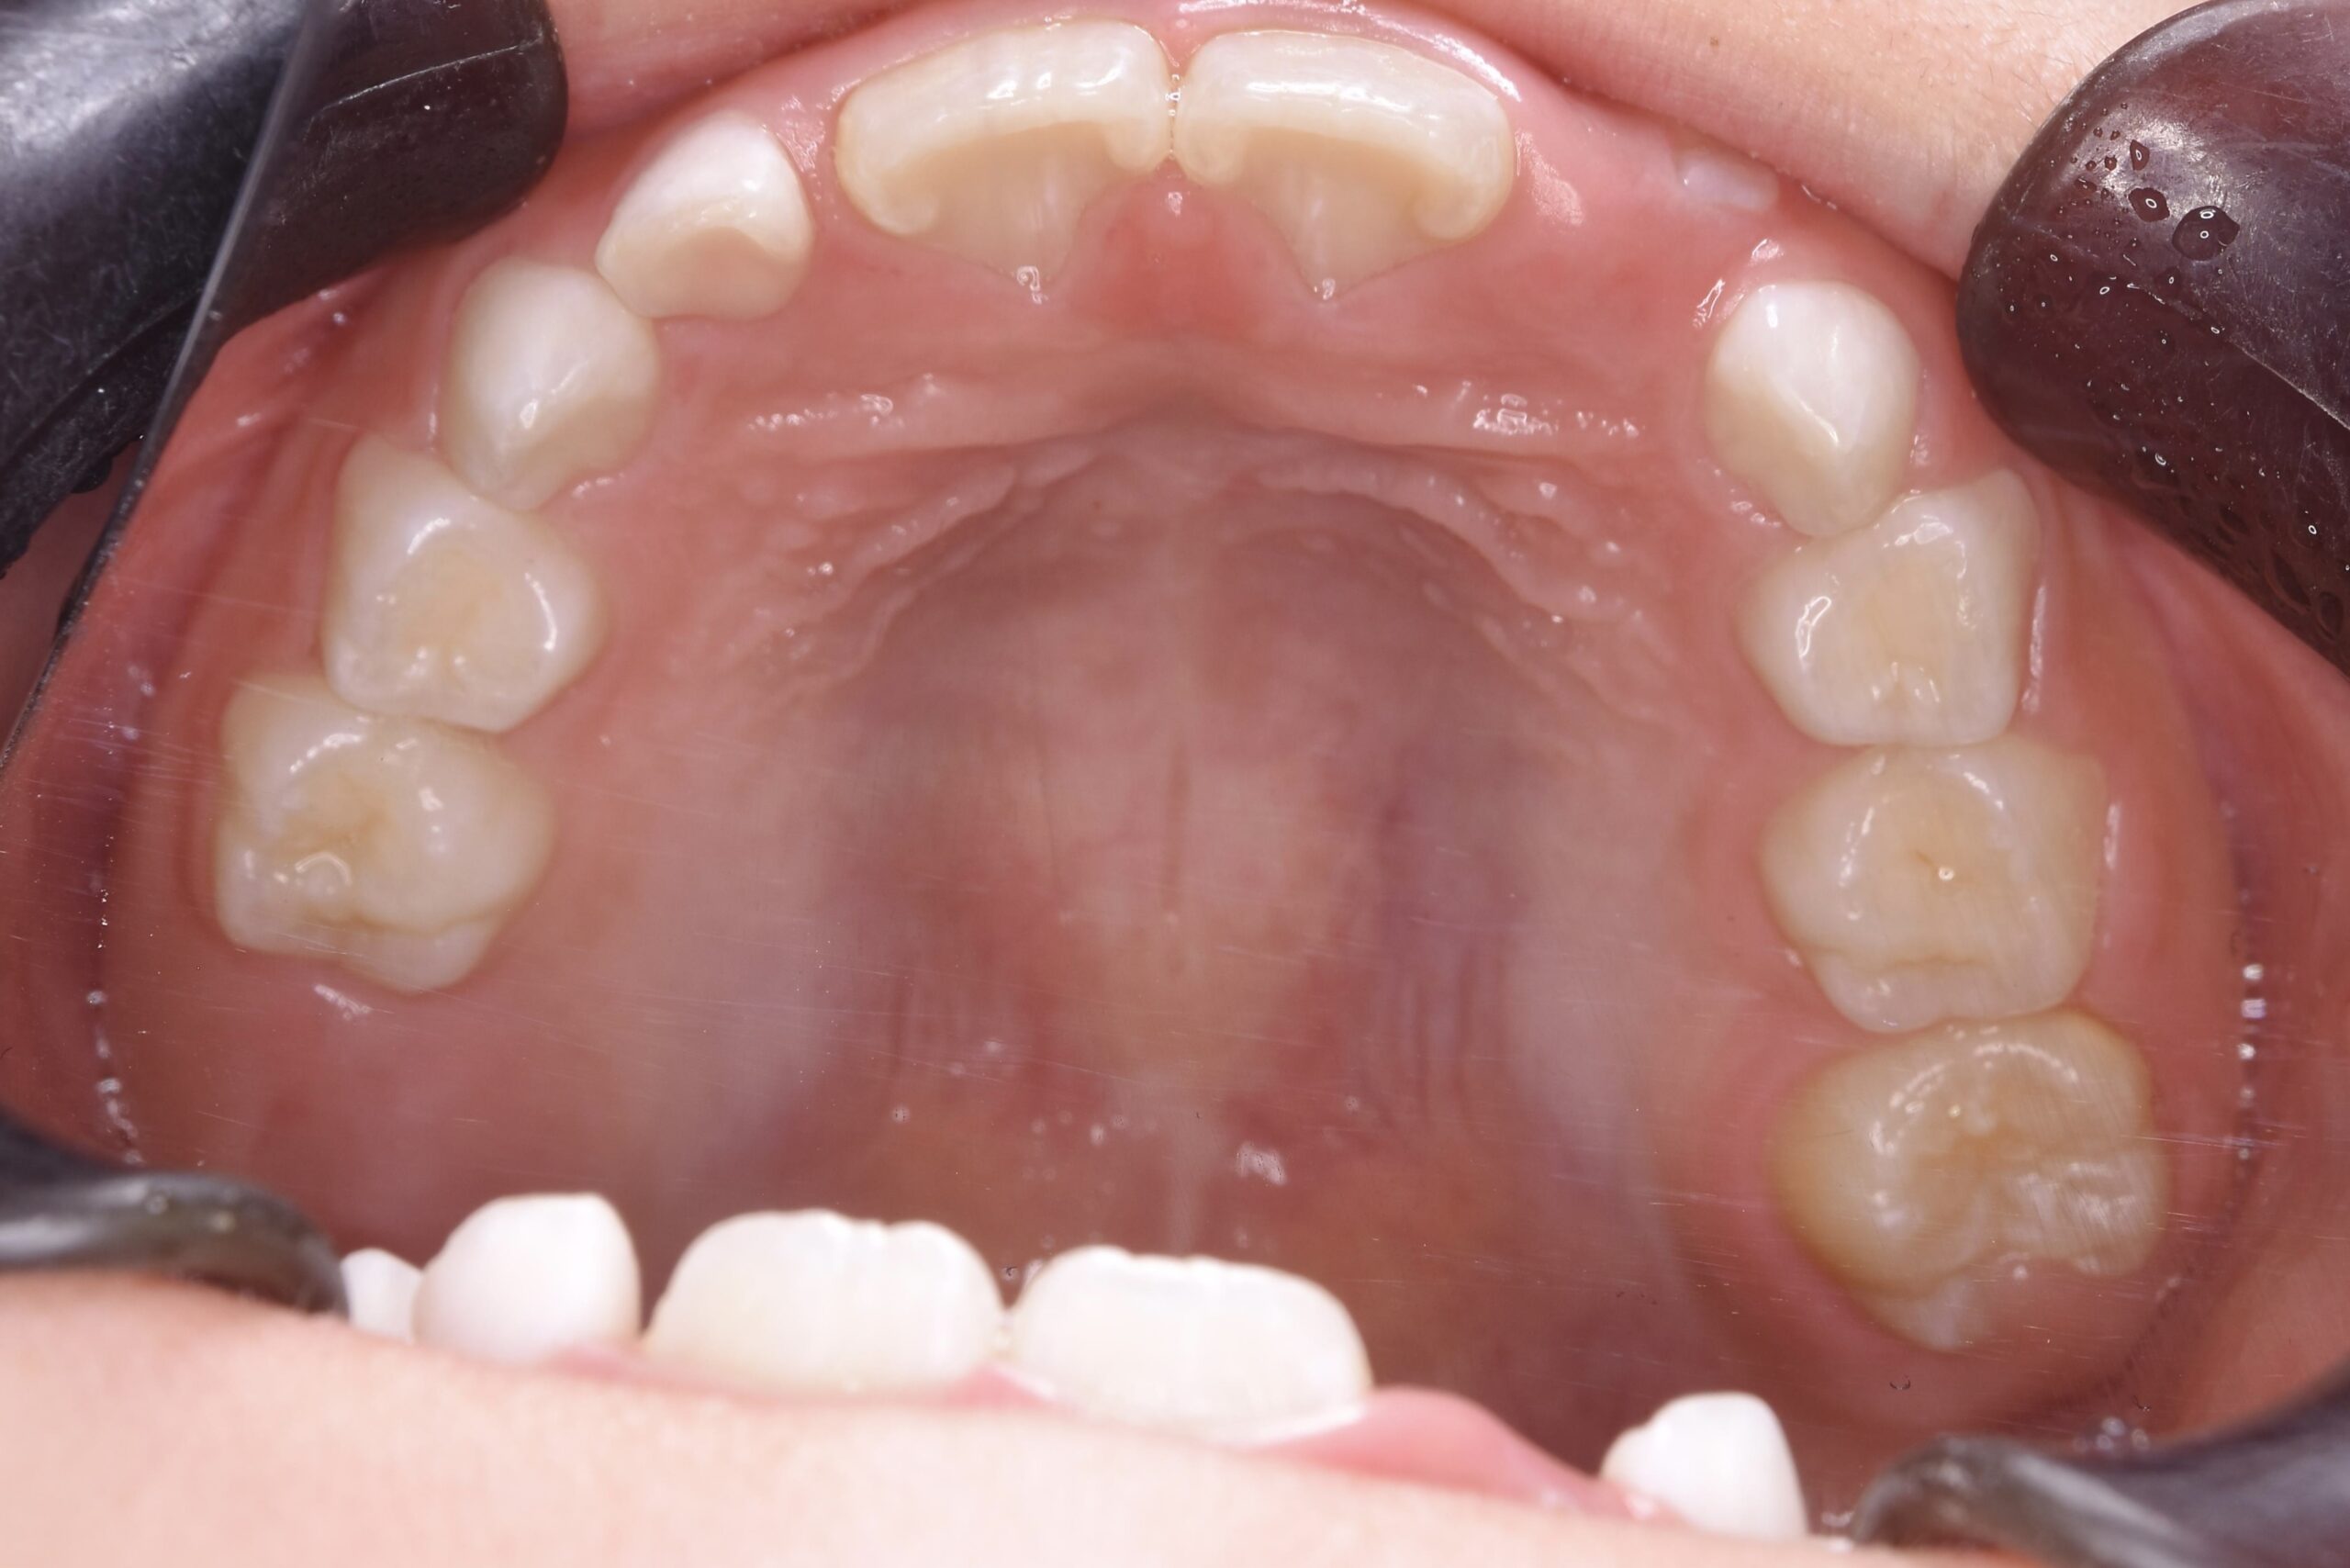

5歳 女児 小児矯正

歯並びの状態:

叢生(ガタガタ)

過蓋咬合(咬み合わせが深い)

BEFORE

AFTER

治療内容

上下の歯並びの幅を拡げつつ、前歯の関係を改善しました。

使用装置

急速拡大装置

リンガルアーチ

機能的矯正装置(マイオブレース)

治療期間

2年 + 後戻り止め期間(5年)